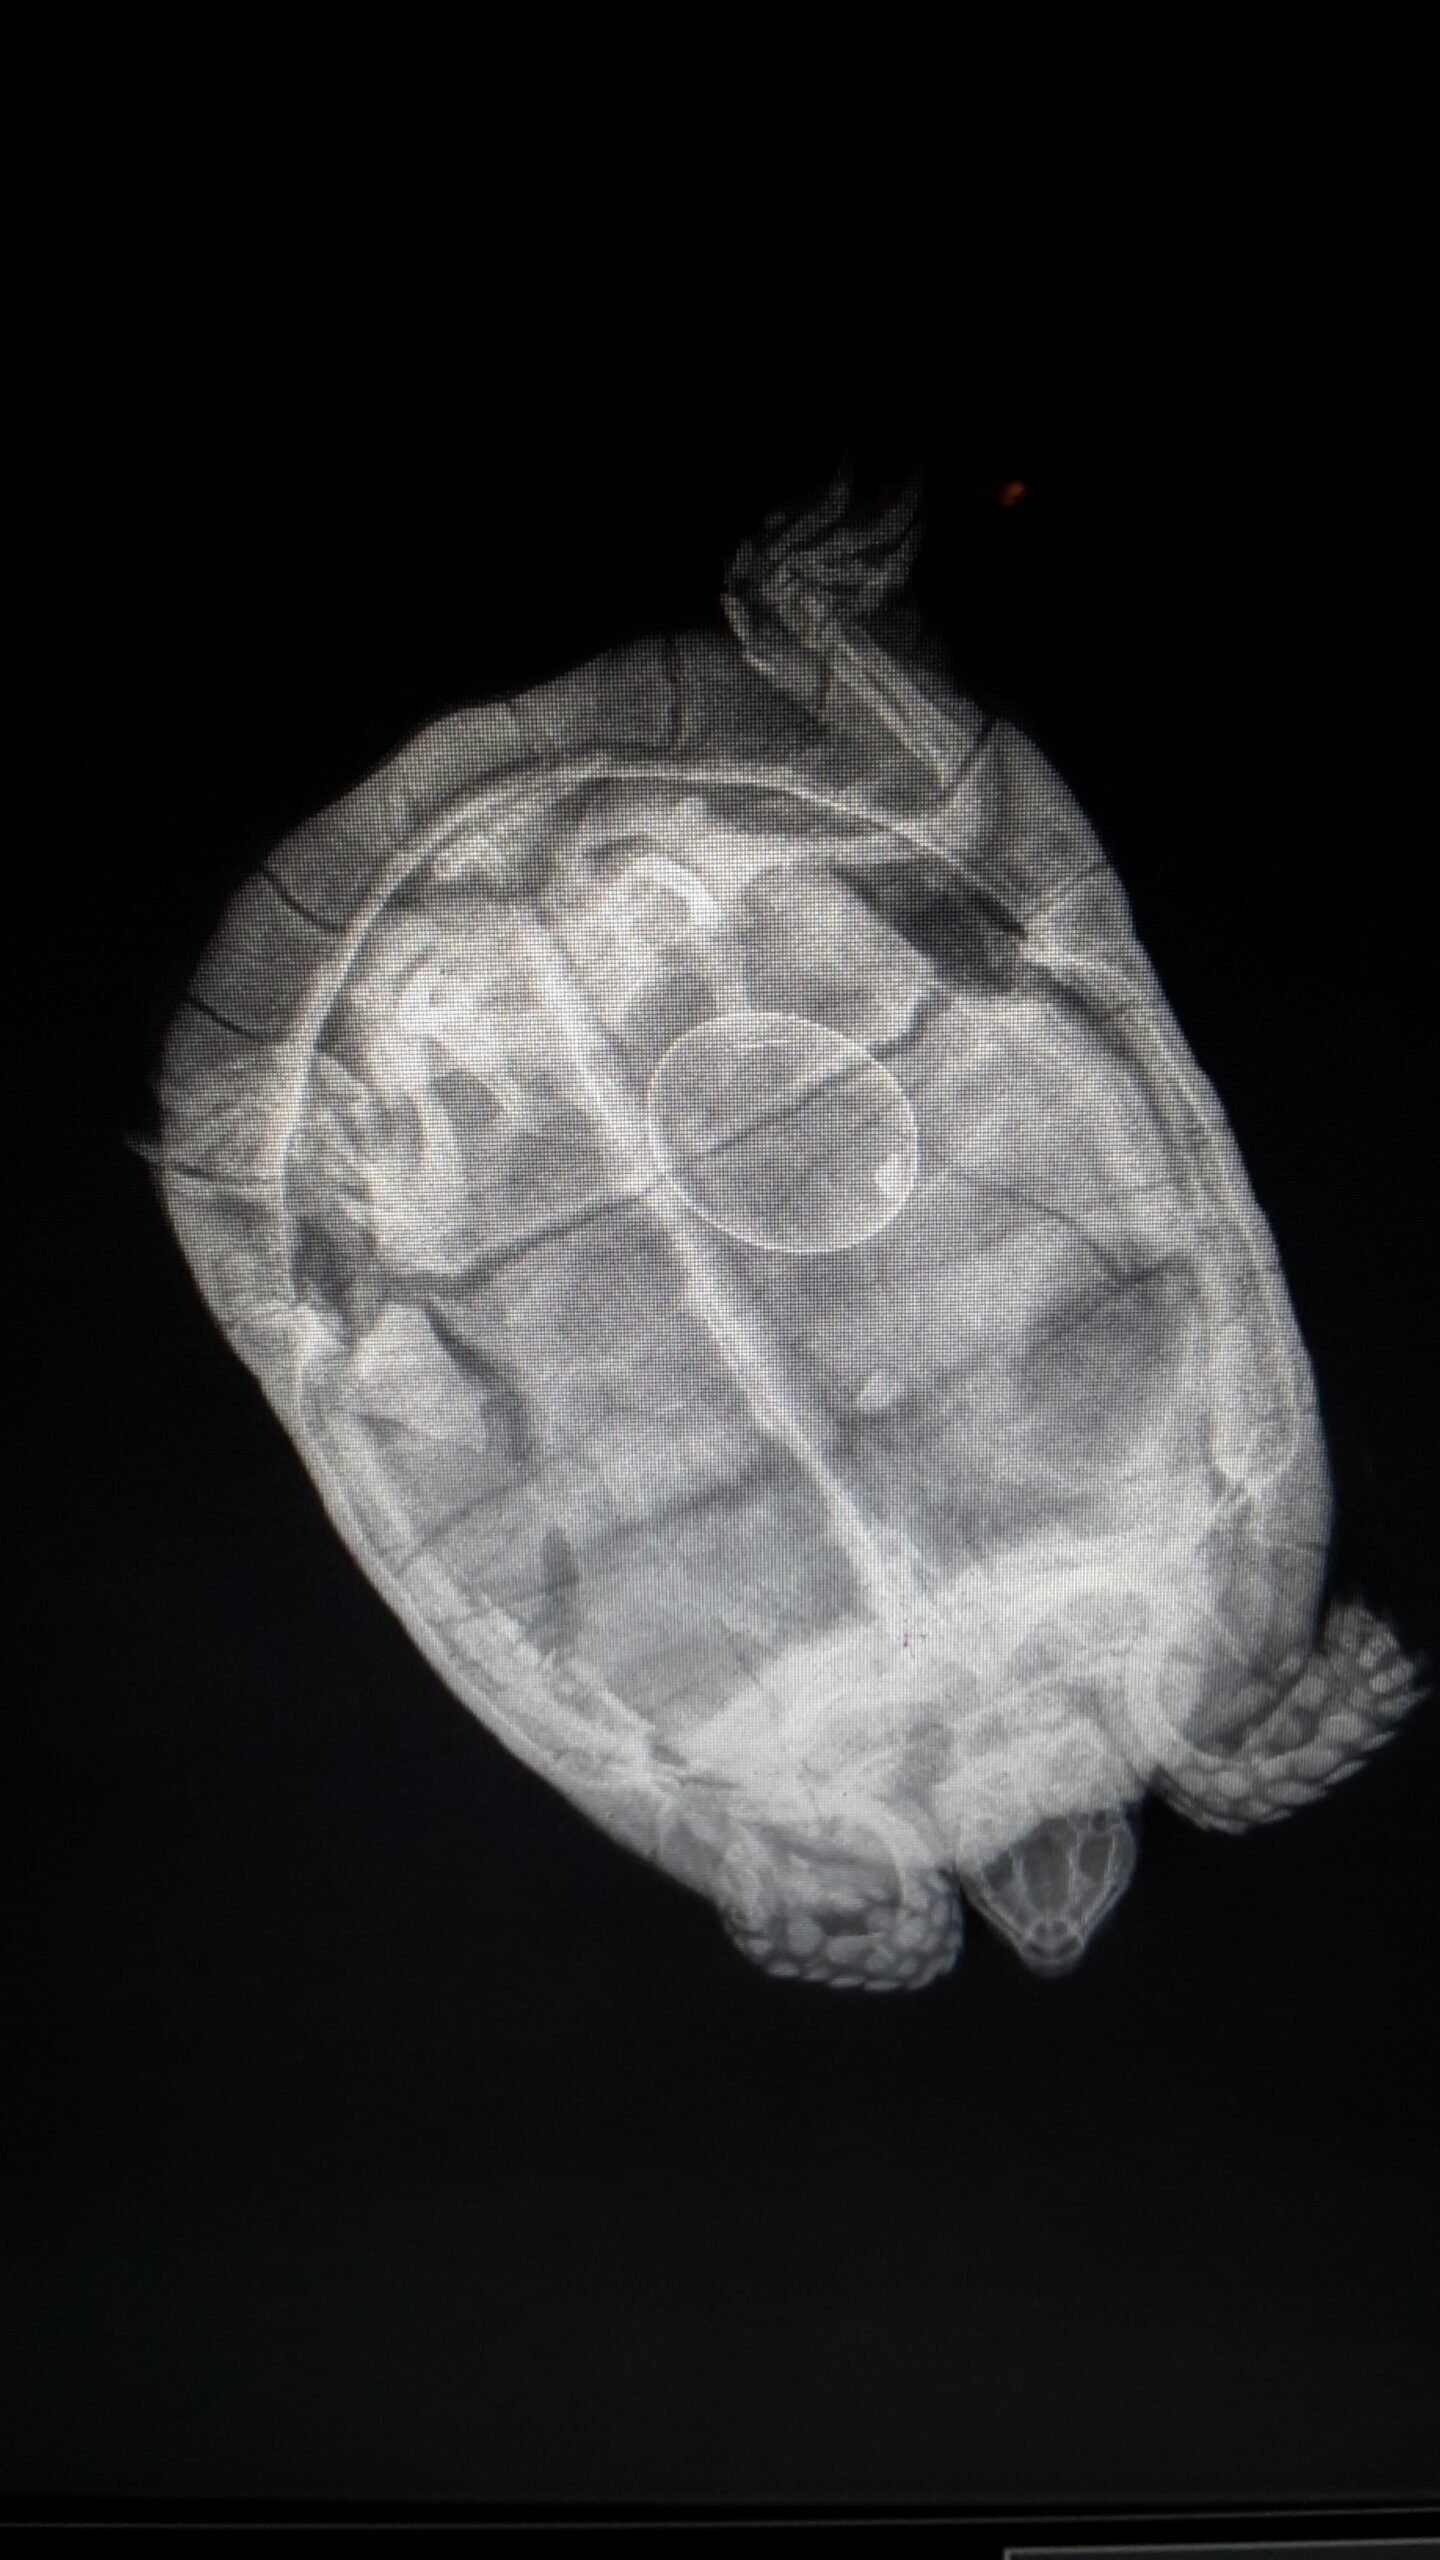

Les examens radiographiques sont effectués au sein de la Clinique Vétérinaire du Mail, ils nécessitent fréquemment une tranquillisation de l’animal afin d’obtenir des images de qualité.